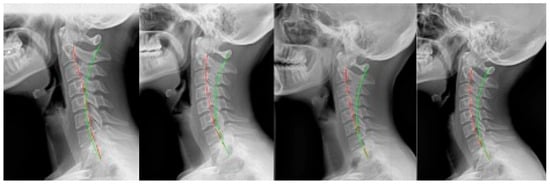

2.2. Case 2

2.3. Case 3

2.4. Case 4

2.5. Case 5